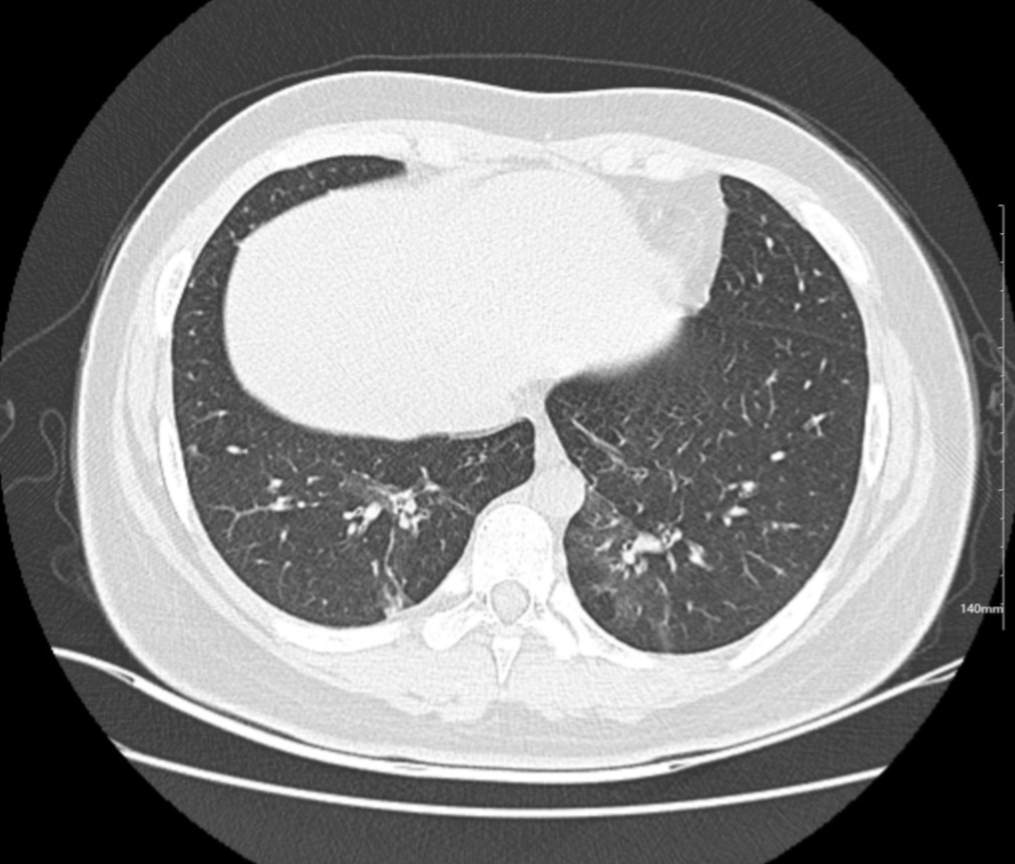

肺部CT:

百日咳肺炎CT 表现

支气管血管束增粗且伴 < 2 个肺叶的磨玻璃密度影, 多提示为单纯性百日咳肺炎。(下图:支气管血管束增粗, 两肺下叶基底段少许磨玻璃密度影)

如出现肺内支气管血管束增粗, 伴≥3 个肺叶斑片影、亚段性实变及支气管气象时, 提示患儿病情较重,可能合并其他感染。